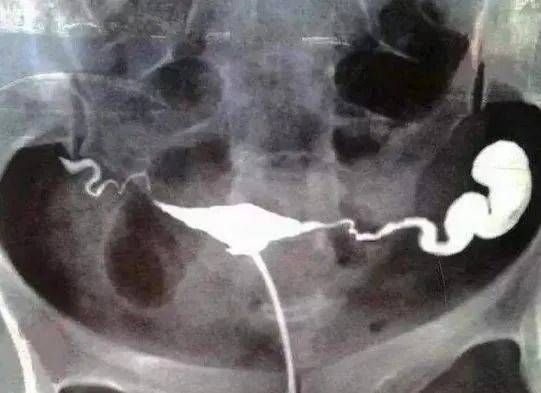

原标题:菏泽做输卵管造影价格新闻热点输卵管造影是一种常见的辅助生育检查方法,用于检测女性输卵管是否通畅。关于输卵管造影的价格和推荐专业生殖医院的问题,我可以给你一些信息。首先,输卵管造影的价格一般受到以下因素的影响:地区因素:不同地区的医疗资源和医疗水平不同,价格可能会有所差异。医院级别:大型专业生...